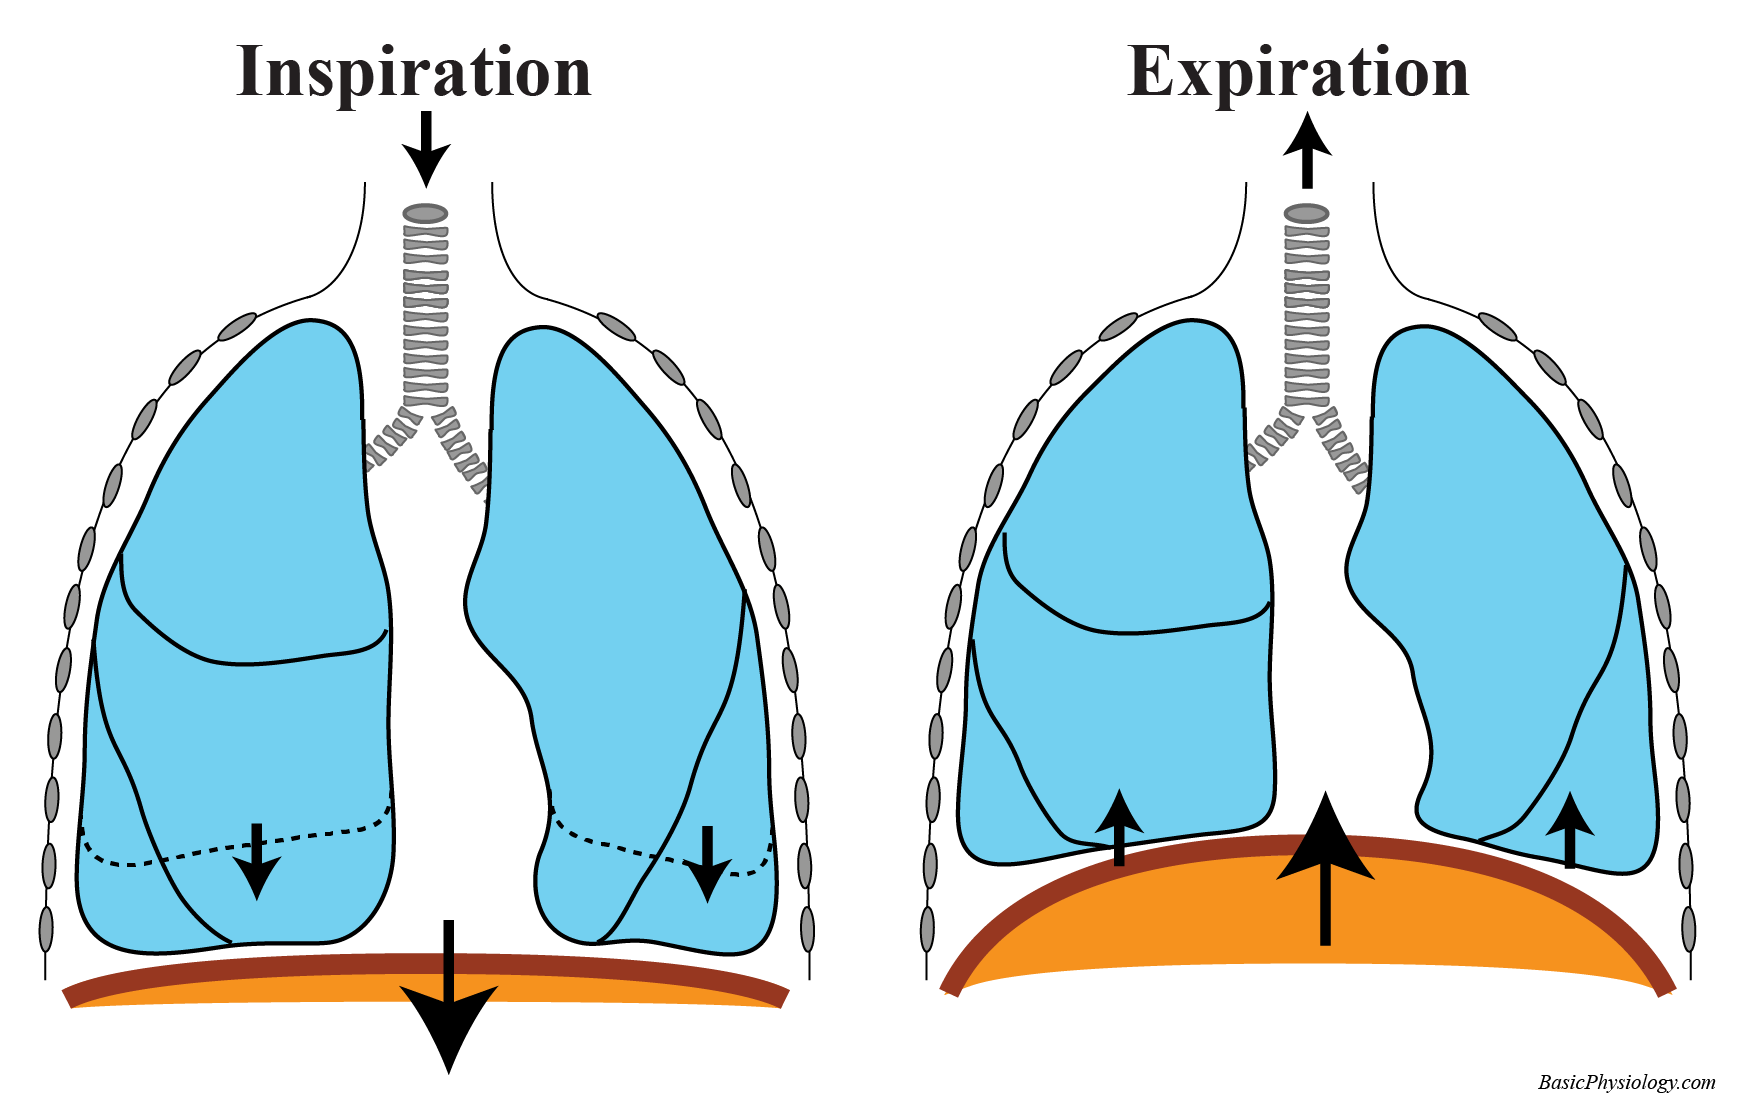

Inspiration And Expiration Chest Size The intercostal muscles contract and move the ribs upwards and outwards This increases the size of the chest and decreases the air pressure inside it which sucks air into the lungs

The diaphragm and external intercostals mediate inspiration and expiration by contracting or relaxing During inspiration the external intercostals and the diaphragm contract expanding the chest wall From a physiological standpoint the lung volumes are either dynamic or static Both subclasses are measured at different degrees of inspiration or expiration however dynamic lung volumes

Changing Thoracic Volume

The intercostal muscles contract and move the ribs upwards and outwards This increases the size of the chest and decreases the air pressure inside it which sucks air into the lungs

Inspiration And Expiration Chest Size - The diaphragm and external intercostals mediate inspiration and expiration by contracting or relaxing During inspiration the external intercostals and the diaphragm contract expanding the chest wall